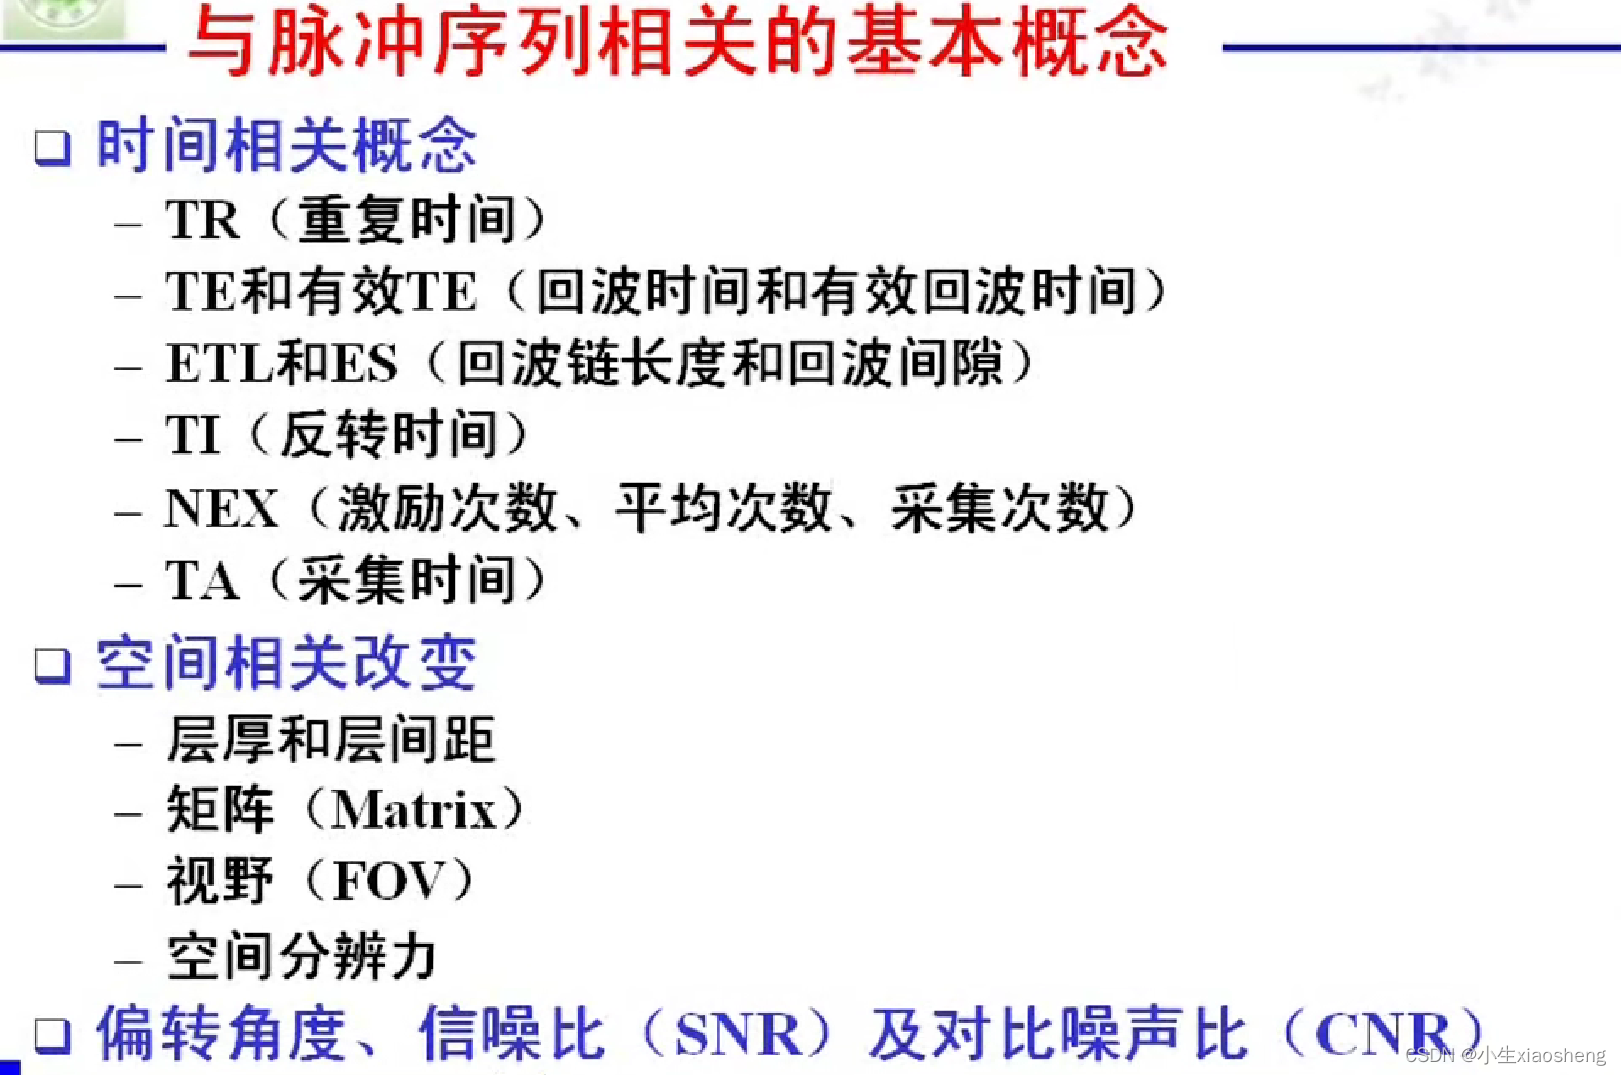

TR代表重复时间(repetition time),是指脉冲序列执行所需的时间

TE代表回波时间(echo time),是指产生宏观横向磁化矢量的脉冲中点到回波中点的时间间隔

因为这里有很多的180度,所以一次能填充很多K空间线。两个90度之间的时间还是叫做TR,180度的个数叫做ETL,90度到中间个数的180度叫做有效TE,两个180度之间的叫做ES。

说明时间越长对应的差距也就越大,说明其结果对比好,更容易看出图片。其中TI为反转时间